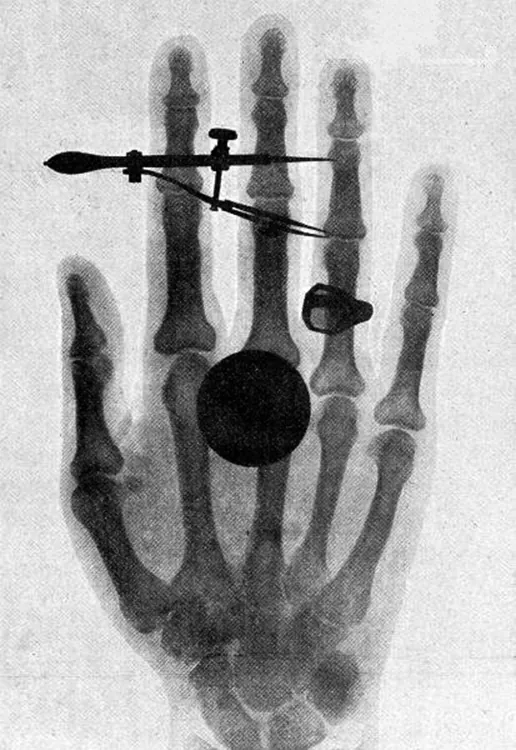

An x-ray image of Bertha Röentgen’s hand is shown with a dark circular spot superimposed on the fingers.

Figure 29.10 One of the first x-ray images, taken by Röentgen himself. The hand belongs to Bertha Röentgen, his wife. (credit: Wilhelm Conrad Röntgen, via Wikimedia Commons)

High photon energy also enables γγ rays to penetrate materials, since a collision with a single atom or molecule is unlikely to absorb all the γγ ray’s energy. This can make γγ rays useful as a probe, and they are sometimes used in medical imaging. x rays, as you can see in Figure 29.9, overlap with the low-frequency end of the γγ ray range. Since x rays have energies of keV and up, individual x-ray photons also can produce large amounts of ionization. At lower photon energies, x rays are not as penetrating as γγ rays and are slightly less hazardous. X rays are ideal for medical imaging, their most common use, and a fact that was recognized immediately upon their discovery in 1895 by the German physicist W. C. Roentgen (1845–1923). (See Figure 29.10.) Within one year of their discovery, x rays (for a time called Roentgen rays) were used for medical diagnostics. Roentgen received the 1901 Nobel Prize for the discovery of x rays.